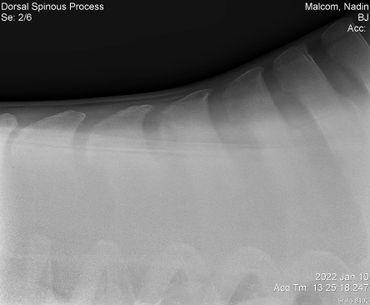

Update 03/04/2022 Billie Jean kept showing some severe sensitivity every time we touched her on her withers and along her spine so back in January we had x-rays taken to check for kissing spine. Everything looked great so we treated her for ulcers with Gastrogard paste and Sucralfate for 7 days.

Her vet bill from January 10 was $445